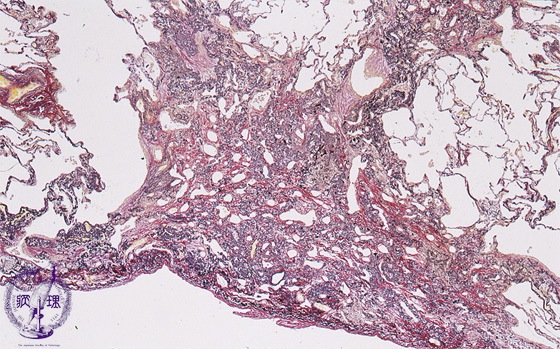

Microscopic view (HE stain, low power view): Long-standing collapse induces fibrosis (collapse fibrosis).